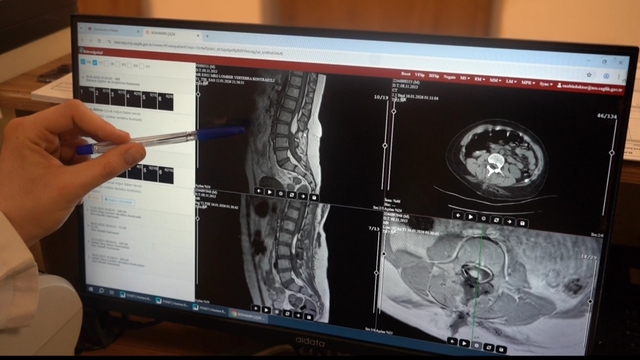

Doğuştan bel bölgesinde kese (meningomyelosel) hastalığı bulunan Bünyamin Çiçek'in şikayetleri artınca ailesi, Batman Eğitim ve Araştırma Hastanesi’ne başvurdu. Beyin ve Sinir Cerrahisi Kliniği'nde yapılan tetkiklerde; omurganın içinde sinirlere baskı yapan ve gergin omurilik (tethered cord) tablosuna yol açan kitle lezyonu tespit edildi. Doktorlar, tablonun ilerlemesi halinde kalıcı felç gelişebileceğini değerlendirerek cerrahi müdahale planladı.

Daha önce ameliyat geçirdiği için cerrahi alanın riskli olduğu belirtilen çocuğun, detaylı planlama ve ileri cerrahi tekniklerle gerçekleştirilen operasyonunda omurilikteki kitle lezyonu boşaltıldı; sinir dokuları ve omurilik üzerindeki baskının tamamen kaldırıldığı bildirildi. Beyin ve Sinir Cerrahisi Uzmanı Op. Dr. Hüseyin Ömer Semiz ve ekibinin gerçekleştirdiği ameliyatın 5 saat sürdüğü, Batman'da ilk kez bel omurga kemiklerine laminoplasti tekniğinin uygulandığı kaydedildi. Operasyonun omurgaya vida ya da platin yerleştirilmeden tamamlandığı, böylece omurganın doğal yapısının korunarak çocuğun ilerleyen yıllardaki boy uzaması ve fiziksel gelişiminin desteklendiği belirtildi.

Operasyonla ilgili bilgi veren Op. Dr. Hüseyin Ömer Semiz, "11 yaşında erkek hastamızın belinde omurilik sinirlerine yapışık bir tümör saptadık. Yaşı ilerledikçe ve boyu uzadıkça sinirlere zarar verebileceği için cerrahi planladık. Ameliyatımız 5 saat sürdü. Tümörü olabildiğince tamamen çıkardık. Yapışıklıkları açarak hastanın uzamasına engel olabilecek yapıları ortadan kaldırmış olduk. Ameliyat sonrasında hastamız iyi. Herhangi bir kuvvet kaybı, tuvalet sıkıntısı, yürüme sorunu yok. Bu omurga tümörü çok nadir görülmektedir. Bel kemiklerini çıkardıktan sonra tekrar koyma tekniğini kullandık. Bu sayede vida/platin koymamış olduk; boyunun uzamasına engel olmuyor. Sonrasında kemikler iyileşerek eski haline geri dönüyor" dedi.